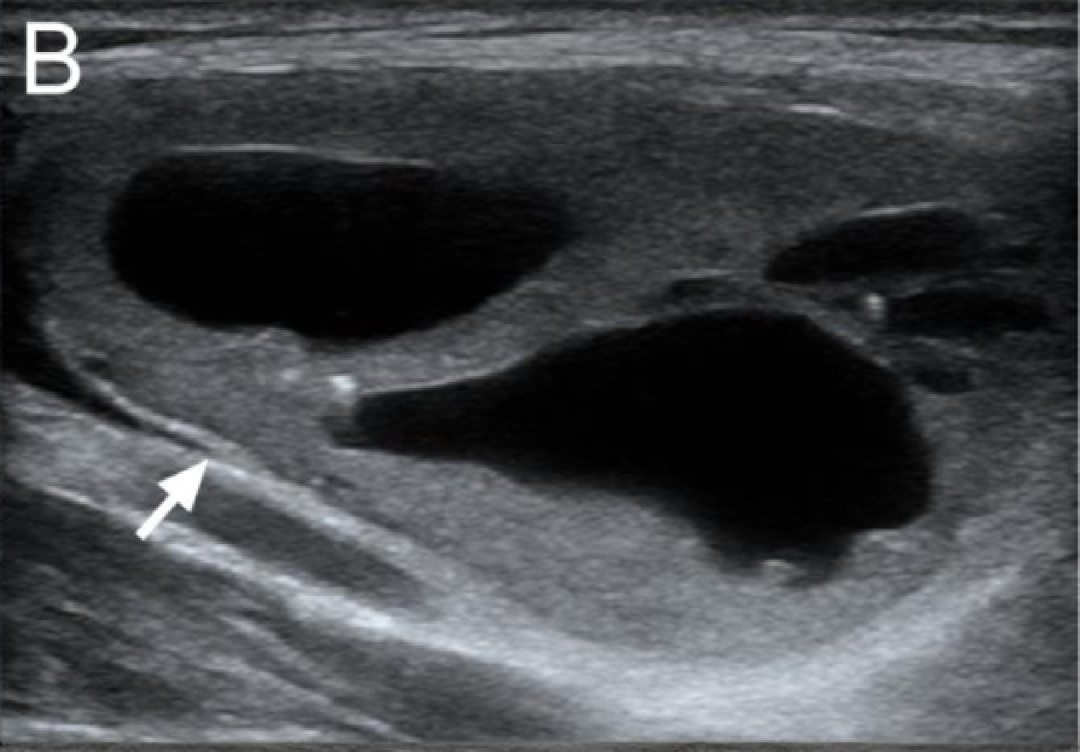

B

C-TIRADS 2 类

海绵状结节。

诊断:结节性甲状腺肿。